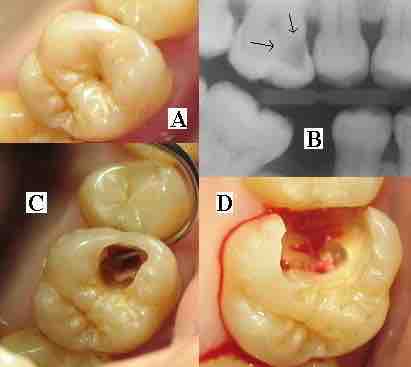

(A) A small spot of decay visible on the surface of a tooth. (B) The radiograph reveals an extensive region of demineralization within the dentin (arrows). (C) A hole is discovered on the side of the tooth at the beginning of decay removal. (D) All decay removed.

As the enamel and dentin are destroyed, the cavity becomes more noticeable . The affected areas of the tooth change color and become soft to the touch. Once the decay passes through enamel, the dentinal tubules, which have passages to the nerve of the tooth, become exposed, causing a toothache. The pain may worsen with exposure to heat, cold, or sweet foods and drinks. Dental caries can also cause bad breath and foul tastes. In highly progressed cases, infection can spread from the tooth to the surrounding soft tissues. Complications such as cavernous sinus thrombosis and Ludwig's angina can be life-threatening.